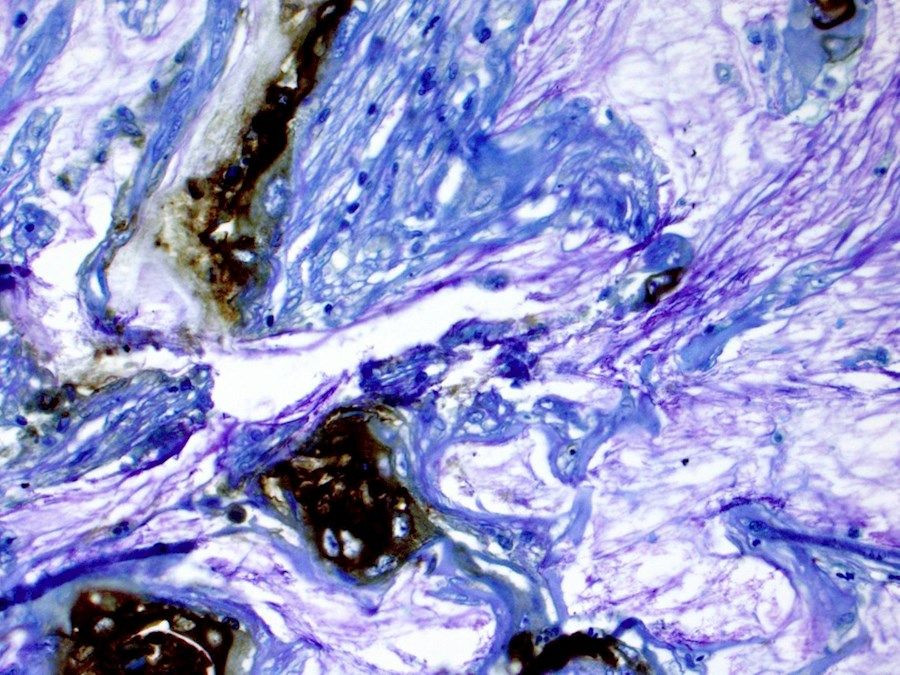

Investigaciones anteriores habían demostrado que el microambiente del tumor pancreático alberga niveles aumentados de CO2. Aquí, el equipo demostró que aumentar el CO2 en cultivos celulares a los niveles observados en pacientes pulmonares era suficiente para aumentar su crecimiento y agresividad.

Cuando estas células con alto contenido de CO2 fueron tratadas con agentes quimioterapéuticos comunes y radioterapia, mostraron una mayor resistencia en comparación con las células cultivadas en condiciones normales de CO2 .